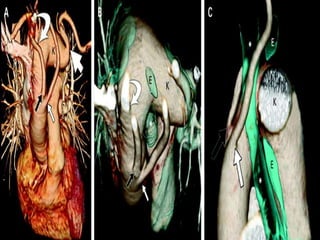

11 children required additional surgery because their vascular ring

(ligamentum) was divided without addressing the associated Kommerell's

diverticulum.

All were symptomatic, with recurrent respiratory symptoms or recurrent

dysphagia.

All patients responded to reoperation with resection of the diverticulum and

transfer of the left subclavian artery to the left carotid artery with resolution of

airway symptoms

The primary strategy for patients with a right aortic arch, left ligamentum,

and Kommerell's diverticulum –

division of the ligamentum,

resection of Kommerell's diverticulum,

left subclavian artery transfer